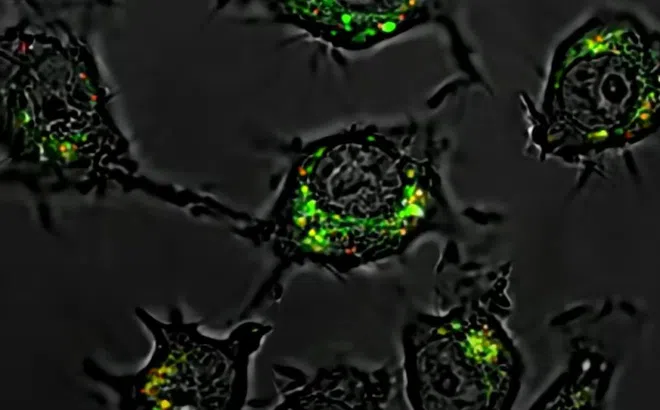

Phát hiện thuốc mới giúp tiêu diệt tế bào ung thư mạnh gấp 20.000 lần

Nhà khoa học Mỹ đang tái cấu trúc thuốc hóa trị quen thuộc, giúp tiêu diệt tế bào ung thư vượt trội nhưng giảm đáng kể độc tính.